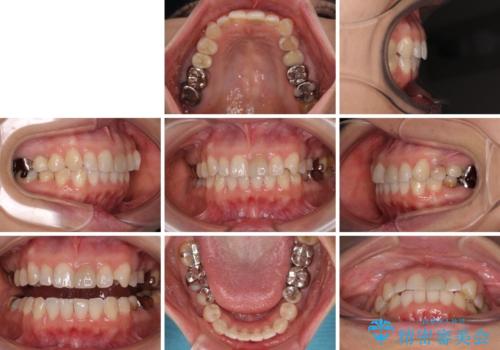

当院では治療前の歯列が整っていない限り、下顎前歯の舌側をワイヤーで固定するようにしています。下顎のみの部分矯正としたことで、マウスピース保定の負担を軽減することができました。

上顎は、失活して歯の色が変色しているため、将来的に補綴治療で自然な口元に仕上げていきたいとのことでした。

矯正治療は、歯の後戻りを抑制するために、治療終了後も保定装置をしっかりと使用していただくことが必須であるため、気になっている下顎だけを整えることで、その負担を半減できると考え、下顎のみの部分矯正として治療を行うこととしました。